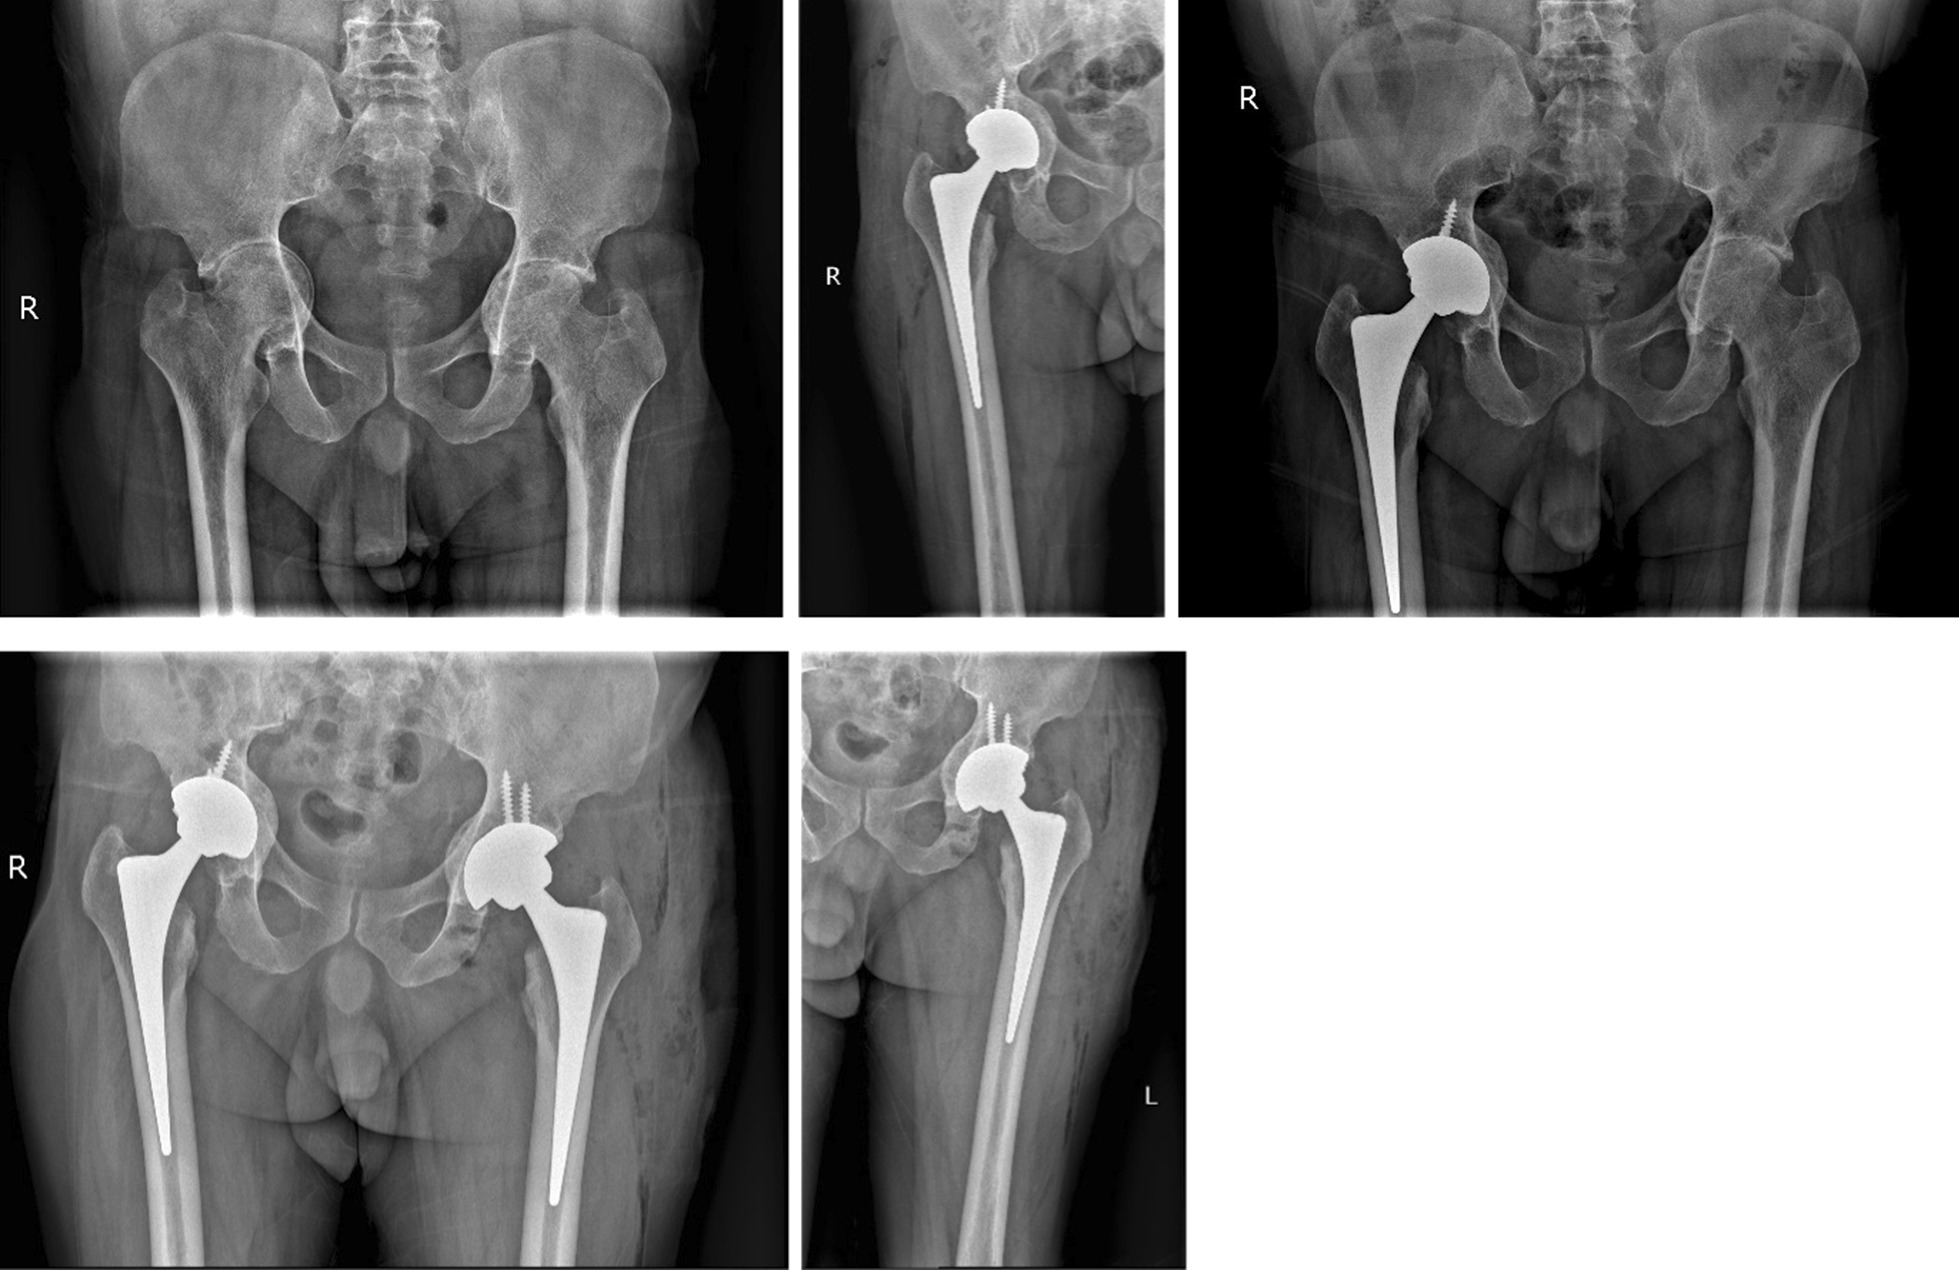

Immediate postoperative anteroposterior pelvic radiographs showed that the acetabular cup and femoral stem prosthesis were well-positioned and firmly fixed in 45 patients (56 hips). The average tilt angle of the acetabulum was 45° (range 39°–50°). In all cases, the x-ray showed that the impacted morselized bone graft was incorporated into the surrounding bone. One-year follow-up x-ray showed continued growth of the trabecular bone through the prosthetic bone interface and fusion of the graft with the host bone. At the last follow-up, the x-ray of all cases showed accurate placement of the prosthesis and good biological fixation between the prosthesis and the bone. There was no obvious transparent area between the prosthesis and bone interface, and the graft was well fused with the host bone. There was no obvious subsidence of the femoral prosthesis or loosening or invagination of the acetabular cup (Fig. 2).

Fig. 2.

A 54-year-old female patient was diagnosed with bilateral acetabular protrusion secondary to RA. (1) Preoperative anteroposterior x-ray of the pelvis showing bilateral femoral heads protruding inward beyond the Kohler’s line. The patient was classified as type II according to Sotello-Garza and Charnley criterion. (2) Cementless THA accompanied by acetabular reconstruction using impacted bone grafting. Immediate postoperativexX-rays revealed that the acetabular prosthesis had a good position and initial stability, and the rotational center of the hip joint had returned to the normal anatomical location. (3) The 5-year follow-up after right hip replacement, there was no obvious loosening of the prosthesis, invagination of the acetabular cup, complete bone graft healing, and no bone resorption. Anteroposterior x-ray of the pelvis showed that left femoral head protruding inward beyond the Kohler’s line, which was classified as type II. (4) postoperative x-rays revealed that bilateral acetabular prosthesis had a good position and stability, and the left hip center had returned to the normal anatomical location; (5) The 2-year follow-up after left hip replacement, there was no obvious loosening of the prosthesis, and invagination of the acetabular cup